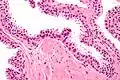

Néoplasie prostatique intraéphithéliale

Néoplasie prostatique intraéphithéliale de haut grade (HGPIN)